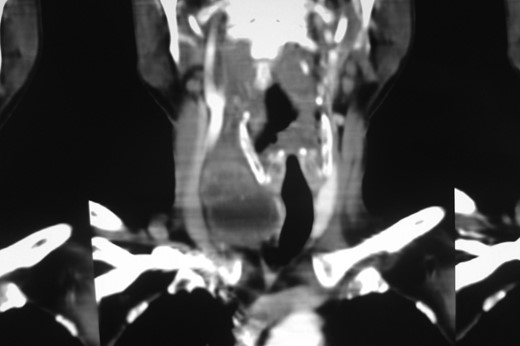

Computed tomography (CT) scan of the neck (with contrast) indicated a heterogeneously enhancing lesion with multiple cystic spaces along the postero-lateral aspect of the right lobe. The lesion was seen to push the adjacent lobe anteriorly to the left (Fig. 2). The lesion was also displacing the right common carotid and the internal jugular vein laterally; however, a well-defined fat plane was seen between the lesion and the carotid sheath. No such plane was seen between the lesion and the adjacent thyroid lobe (Fig. 3).

Contrast enhanced CT neck (coronal section). Coronal section showing good plane of delineation between the lesion and carotid sheath, along with mass effect on the thyroid gland and the right common carotid.